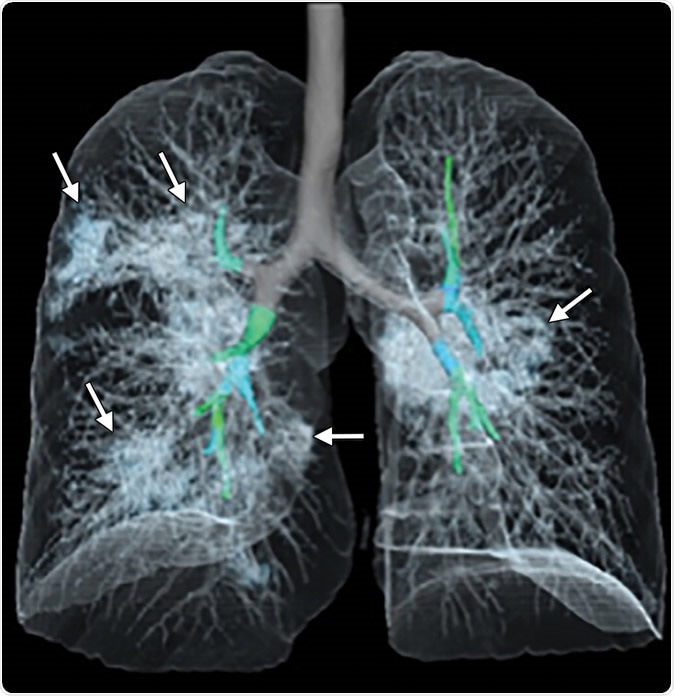

Images in a 41-year-old woman who presented with fever and positive polymerase chain reaction assay for the 2019 novel coronavirus (2019-nCoV). (a) Three representative axial thin-section chest CT images show multifocal ground glass opacities without consolidation. (b) Three-dimensional volume-rendered reconstruction shows the distribution of the ground-glass opacities (arrows). See also three-dimensional Movie (online).

The study examines the chest X-rays, and CT scans from over 20 patients aged 10-74 years, with symptoms of COVID-19. The scans showed inflamed lungs with ground-glass opacities, which look like white lung patches. These opacities are due to the partial clogging of the lung alveoli with tenacious mucus. Autopsies of Chinese patients who died of the illness because of breathing difficulties show lungs with minimal capacity for air inhalation due to the mucus accumulation.